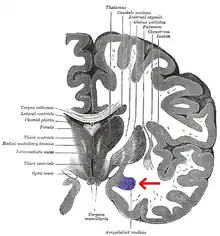

Las regiones descritas como «amígdala» en realidad abarcan una serie de núcleos con distintos atributos funcionales llamada complejo amigdalino. Entre esos núcleos se encuentra el grupo basolateral, el núcleo centromedial y el núcleo cortical. El grupo basolateral se puede dividir a su vez en el núcleo lateral, el basal y los núcleos basales accesorios.[2][4]

El núcleo cortical está relacionado con el sentido del olfato y el procesamiento de las feromonas. Recibe información desde el bulbo olfatorio y la corteza olfatoria. El núcleo lateral, que envía proyecciones al resto del grupo basolateral y a los núcleos centromediales, recibe proyecciones desde sistemas sensoriales. Los núcleos centromediales conforman las principales sales para el grupo basolateral, y está involucrado en la activación emocional en ratas y gatos.[3][4][5]